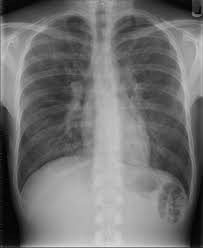

Respiratory disease is a medical term that encompasses pathological conditions affecting the organs and tissues that make gas exchange possible in higher organisms, and includes conditions of the upper respiratory tract, trachea, bronchi, bronchioles, alveoli, pleura and pleural cavity, and the nerves and muscles of breathing. Respiratory diseases range from mild and self-limiting, such as the common cold, to life-threatening entities like bacterial pneumonia, pulmonary embolism, and lung cancer. The study of respiratory disease is known as pulmonology. A doctor who specializes in respiratory disease is known as a pulmonologist, a chest medicine specialist, a respiratory medicine specialist, a respirologist or a thoracic medicine specialist.

Infections can affect any part of the respiratory system. They are traditionally divided into upper respiratory tract infections and lower respiratory tract infections. The most common upper respiratory tract infection is the common cold however, infections of specific organs of the upper respiratory tract such as sinusitis, tonsillitis, otitis media, pharyngitis and laryngitis are also considered upper respiratory tract infections. The most common lower respiratory tract infection is pneumonia, an infection of the lungs which is usually caused by bacteria, particularly Streptococcus pneumoniae in Western countries. Worldwide, tuberculosis is an important cause of pneumonia. Other pathogens such as viruses and fungi can cause pneumonia for example severe acute respiratory syndrome and pneumocystis pneumonia. A pneumonia may develop complications such as a lung abscess, a round cavity in the lung caused by the infection, or may spread to the pleural cavity.